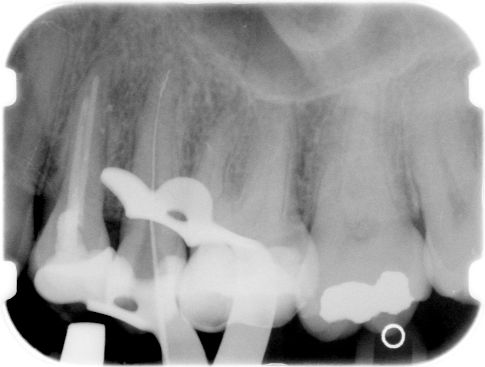

ad c. Een vijl die dicht bij de apex is afgebroken.

Bij een afgebroken vijl in het apicale gebied moest tot voor kort de afweging worden gemaakt of verwijderen niet meer schade berokkende dan laten zitten. Zeker in kromme kanalen was het vrijwel ondoenlijk om én het afgebroken vijltje te verwijderen én de radix te sparen. Passeren en verwijderen van het vijldeeltje is de beste oplossing. De manier waarop is te zien in dit

filmpje. (Let op, de grootte van het bestand is 13 Mb.)